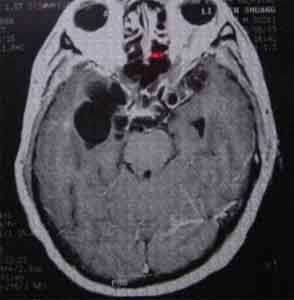

1、X線檢查:小腿軟組織X線攝片,多能發現囊蟲結節鈣化影。2、CT或MRI檢查:特別是MRI檢查,能顯示顱內單個或多個囊蟲影。

由寄生蟲蟲體、蟲卵或幼蟲侵入腦內引起過敏炎症、內芽腫形成或腦血管阻塞的腦病。原為寄生蟲病病人,病程中出現腦病症狀。有:①腦血管吸蟲病,蟲卵隨血行入腦而起。②腦蘘蟲病,豬絛蟲幼蟲蘘尾蚴寄生於腦引起。③顱內包蟲病犬絛蟲幼蟲蚴寄生於顱內所致。④腦肺吸蟲病,成蟲侵入腦內並在腦內移行引起。⑤腦型疝疾,疝原蟲阻塞腦內毛細血管引起。臨床表現:可為急性腦膜腦炎,或為局限性癲癇發作或伴有定位體徵的顱內高壓症,亦可為智慧型衰退或精神障礙。建國前本病呈地區流行,現已少見。診斷依據疫區感染史及腦外該寄生蟲病病史、血和腦脊液酸性細胞增多,抗原皮內試驗和血清補體結合試驗陽性,腦血管造影或顱腦CT可發現病灶。按各該寄生蟲病治療,必要時外科手術。